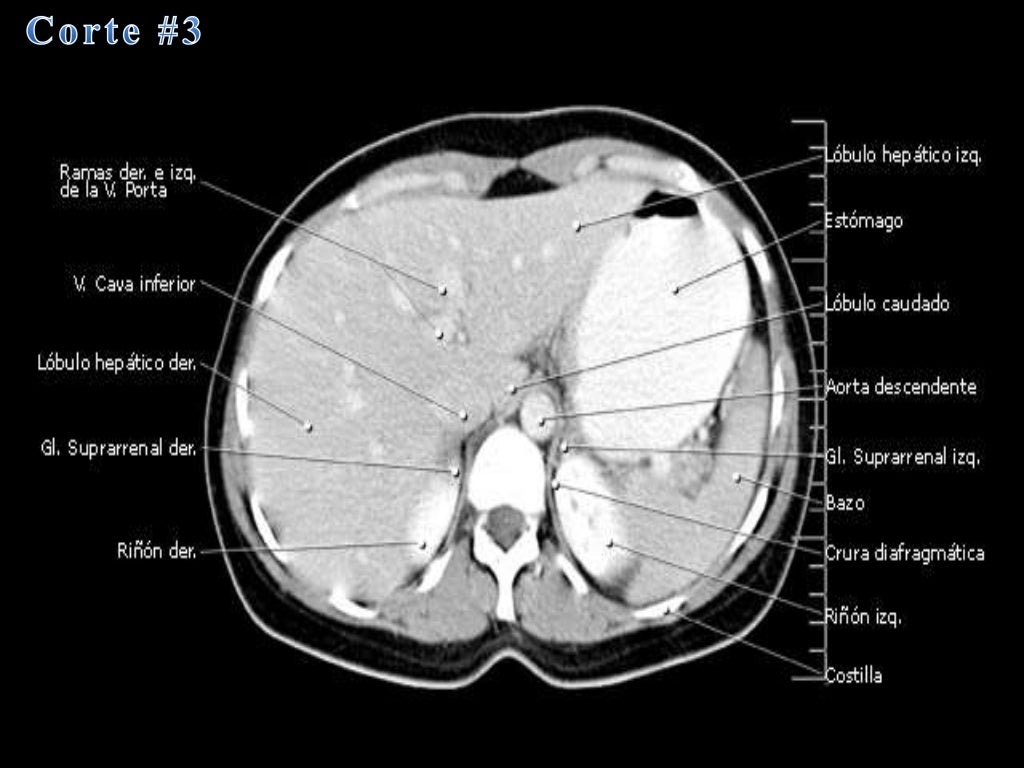

La tomografía computarizada, más comunmente conocida como exploración por tc o tac, es un examen médico de diagnóstico por imágenes.

que es una tomografia abdominal La tomografía computarizada, más comunmente conocida como exploración por tc o tac, es un examen médico de diagnóstico por imágenes. La angiotomografía computarizada del corazón es una forma útil de detectar arterias coronarias obstruidas. Una tomografía computada abdominal utiliza una máquina especial de rayos x para tomar imágenes del hígado, bazo, riñones, vejiga, estómago, intestinos, páncreas y glándulas. Una tomografía de abdomen es un estudio de imagen que ayuda a detectar problemas de salud en el área del abdomen. Una tomografía computada abdominal utiliza una máquina especial de rayos x para tomar imágenes del hígado, bazo, riñones,. La tomografía computarizada, tc, es un procedimiento con imágenes que usa equipo especial de rayos x para crear imágenes detalladas, o exploraciones, de regiones. Al igual que los rayos x. La angiotomografía computarizada podría costar menos que una.